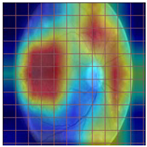

3.2. Models Explainability on the Test Set

| Original Image | VGG16 | ResNet-18 | DenseNet-121 |

|---|---|---|---|

![]() | ![]() | ![]() | ![]() |

| (a) | |||

| (b) | |||

| (c) | |||

| (d) | |||

| Model | Conformity with Normal Retinal Photos | Conformity with Abnormal Retinal Photos | Average Conformity |

| VGG16 | 0.2000 | 0.2414 | 0.2207 |

| ResNet-18 | 0.0294 | 0.0645 | 0.0469 |

| DenseNet-121 | 0.0385 | 0.0286 | 0.0336 |